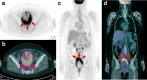

Uterine epithelioid angiosarcoma can have conventional imaging characteristics similar to those of other uterine tumors, such as leiomyoma, leiomyosarcomas or hemangioendothelioma. Uterine epithelioid angiosarcoma exhibiting increased fluorine-18 fluorodeoxyglucose (F-18 FDG) activity can be misdiagnosed. A 61-year-old woman who was diagnosed with uterine epithelioid angiosarcoma underwent F-18 FDG positron emission tomography/computed tomography (PET/CT) as a part of the pretreatment work up for surgery. F-18 FDG PET/CT showed an intense F-18 FDG uptake in the uterus in addition to increased F-18 FDG uptake at the paraaortic and aortocaval lymph nodes. To our knowledge, this is the first case report of intense F-18 FDG uptake in uterine epithelioid angiosarcoma in Korea.